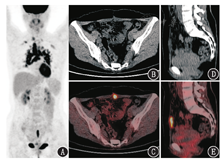

患者女,28岁,宫颈癌术后6个月,左侧腰部疼痛3周。患者6个月前因宫颈鳞状细胞癌(简称鳞癌)行腹腔镜下广泛全子宫切除术+双侧输卵管切除+双侧卵巢悬吊术+盆腔淋巴结及腹主动脉旁淋巴结切除术,术后病理为宫颈中~高分化鳞癌,pT1b1N0M0[国际妇产科联盟(International Federation of Gynecology and Obstetrics, FIGO)分期ⅠB1期]。因病理结果无高危因素,术后未行放化疗。患者3周前无明显诱因出现左侧腰部疼痛,泌尿系统超声提示左肾积水、左侧输尿管轻度积水,血清鳞癌抗原正常。为评估肿瘤复发或转移情况,患者行18F-脱氧葡萄糖(fluorodeoxyglucose, FDG)PET/CT显像,结果示左侧髂内血管旁代谢异常增高的淋巴结,大小为2.4 cm×2.1 cm,最大标准摄取值(maximum standardized uptake value, SUVmax)为17.4,累及相邻输尿管,致其上方输尿管及肾盂扩张、积水;另见左腰大肌前方稍低密度的代谢增高灶,大小为3.7 cm×1.8 cm,SUVmax为5.8(图1)。宫颈癌术后复发的主要部位仍为腹盆腔内,既可因局部肿瘤生长在阴道残端复发,所以需要关注阴道残端是否有代谢异常或组织增厚;也可出现区域淋巴结转移,包括宫旁、髂内/闭孔、髂总/髂外及骶前/骶旁淋巴结,而后可扩散至腹主动脉旁淋巴结群,淋巴结转移的风险随着局部累及程度(T分期)而增高[1]。结合患者宫颈癌病史及近期新出现的肾积水,左髂内血管旁代谢增高的肿大淋巴结,考虑宫颈癌转移灶可能性大,其毗邻并侵及输尿管,造成左肾积水。而左侧腰大肌前方的代谢增高灶按其部位、代谢活性也有可能是另一转移灶,但仔细观察CT图像可发现该病变密度较低。

患者后行腹式肿瘤细胞减灭术+左侧输尿管膀胱再植术+卵巢活组织检查(简称活检)术。术中左髂可触及质硬结节,大小约为2.0 cm×1.5 cm,该处上段输尿管扩张,术后病理为鳞癌,累及左侧输尿管;术中另可见左侧卵巢悬吊于髂棘上方约5.0 cm腰大肌处腹膜,活检为卵巢组织,未见癌。通过手术病理证实左髂代谢增高的淋巴结为宫颈癌转移,而左腰大肌前方代谢增高的低密度结节为正常卵巢。